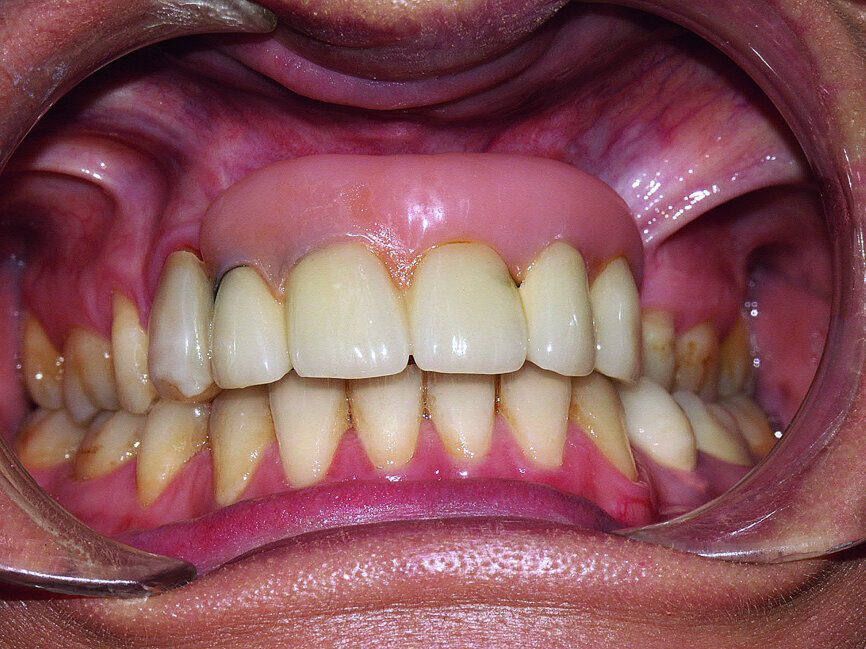

The original treatment consisted of placing two implants in the residual bone and an anchorage reinforcement screw-retained bridge to maintain a removable prosthesis, which included five teeth and a large false gingiva (Fig. 1).

Fig. 1 : Initial prostheses: Lip support was ensured by a large false gingiva, and fractured cosmetic material at the right maxillary canine was evident. The patient’s smile showed the prosthetic teeth placed off-centre and an infiltration at the right lateral incisal level.

Fig. 2 : Initial prostheses: Lip support was ensured by a large false gingiva, and fractured cosmetic material at the right maxillary canine was evident. The patient’s smile showed the prosthetic teeth placed off-centre and an infiltration at the right lateral incisal level.

Dissatisfied with the treatment, the patient was re-examined three years after the initial treatment. The patient’s smile showed an infiltration at the right lateral incisal level and that the prosthetic teeth were placed off-centre. The lip support, ensured by a large false gingiva, was correct. The cosmetic material of the right maxillary canine was fractured (Figs. 1 & 2).